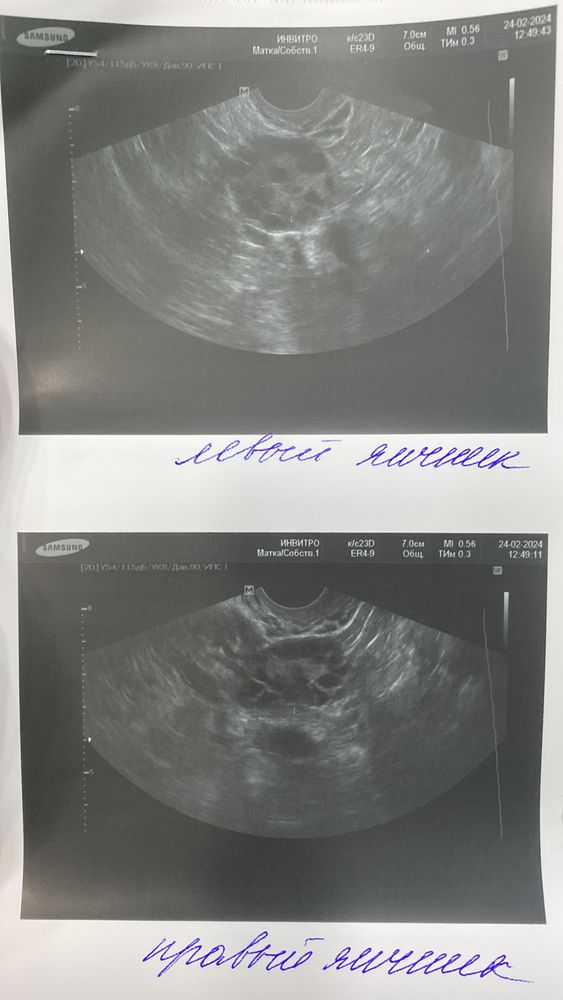

У меня уже есть 2 сыновей, с мужем планируем 3 ребенка. Был не регулярный цикл из за лишнего большого веса. Прописали пить клайру и на отмене беременеть. Делать тест на овуляцию начала с 10 ДЦ все в итоге 4-5 дней положительные .

последние месячные были 22.01.